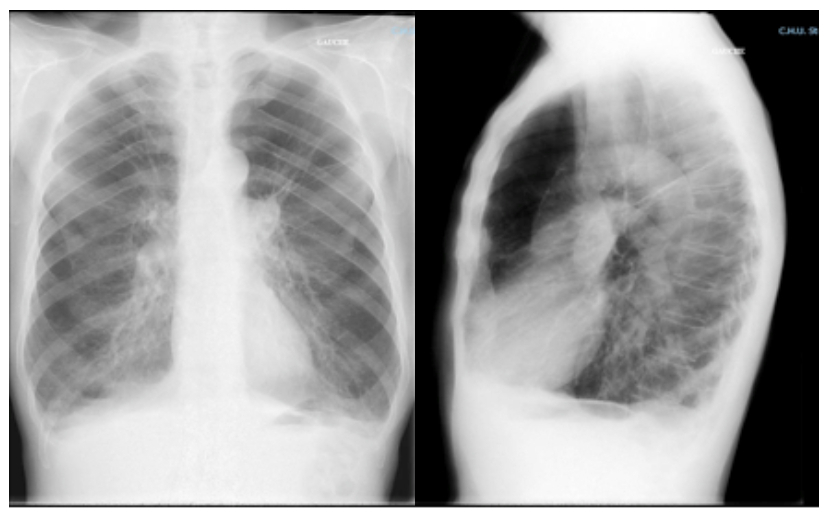

Le patient retourne à domicile. Il est suivi par un pneumologue qui le revoit à 6 mois de son hospitalisation. Il reste très symptomatique malgré le traitement de fond par bronchodilatateur de longue durée d’action seul bien conduit et la réhabilitation respiratoire. Il se plaint beaucoup d’un encombrement bronchique avec bronchorrhée. Il n’a pas refait d’exacerbation ces 6 derniers mois. Entre-temps il a vu un cardiologue qui lui a prescrit un bêtabloquant cardio-sélectif. Le pneumologue lui prescrit un scanner qui est le suivant.

Figure 5.

Question 10 - Quelle(s) affirmation(s) est/sont juste(s) ?

Il s’agit ici d’un emphysème bulleux typique : zones d’hypodensité traduisant une raréfaction du parenchyme pulmonaire. On parle de bulle quand les zones d’hypodensité sont cerclées par une paroi fine et ont un diamètre de plus de 1 cm.

Un déficit en alpha-1 antitrypsine est à suspecter devant :

– un emphysème majeur prédominant ;

– une BPCO précoce (< 45 ans) ;

– une BPCO chez un patient non ou peu tabagique ;

– des antécédents familiaux.

Il s’agit de la seule prédisposition génétique de la BPCO connue jusqu’à présent. Il est important de faire le diagnostic pour la descendance et car il est possible d’envisager une supplémentation en alpha-1 antitrypsine.